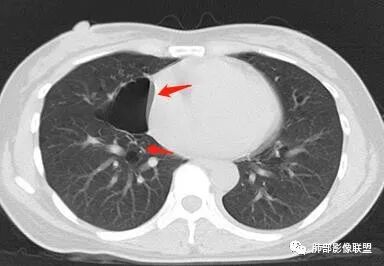

女,38岁,无症状,胸片体检发现两肺可疑病灶。

?其母亲有肺大泡,2017年手术。影像学特点:两肺胸膜下多发的大小不等囊状气腔,壁很薄或无可见的囊壁,小囊的边界比较清楚,大囊的形态比较怪异,以两下肺为著。考虑肺组织细胞增生症,鉴别肺淋巴管肌瘤病。

小叶中心,胸膜下囊,比较大,规则:

这个图好,下次我们就这样的不是叶间胸膜,而是胸膜下囊

BHD主要影像表现特征:    1、两肺内肺囊肿:80%以上的BHD患者会出现肺内囊肿,且倾向于基底部近胸膜下分布,特别是纵膈侧肺膜下,囊肿形状不规则、囊肿可大可小,肺内囊肿多毗邻肺下动脉或静脉近端,胸部CT上囊肿分布和特点对诊断有提示意义。    2、继发自发性气胸:BHD患者发生气胸风险是正常人的5倍,BHD患者的气胸发生率约为 1/4,气胸复发率则高达59%。   3、肾肿瘤:(常为双侧性、倾向于嫌色细胞组织学亚型)   4、皮肤表现(为面、颈部纤维性毛囊瘤、毛盘瘤)